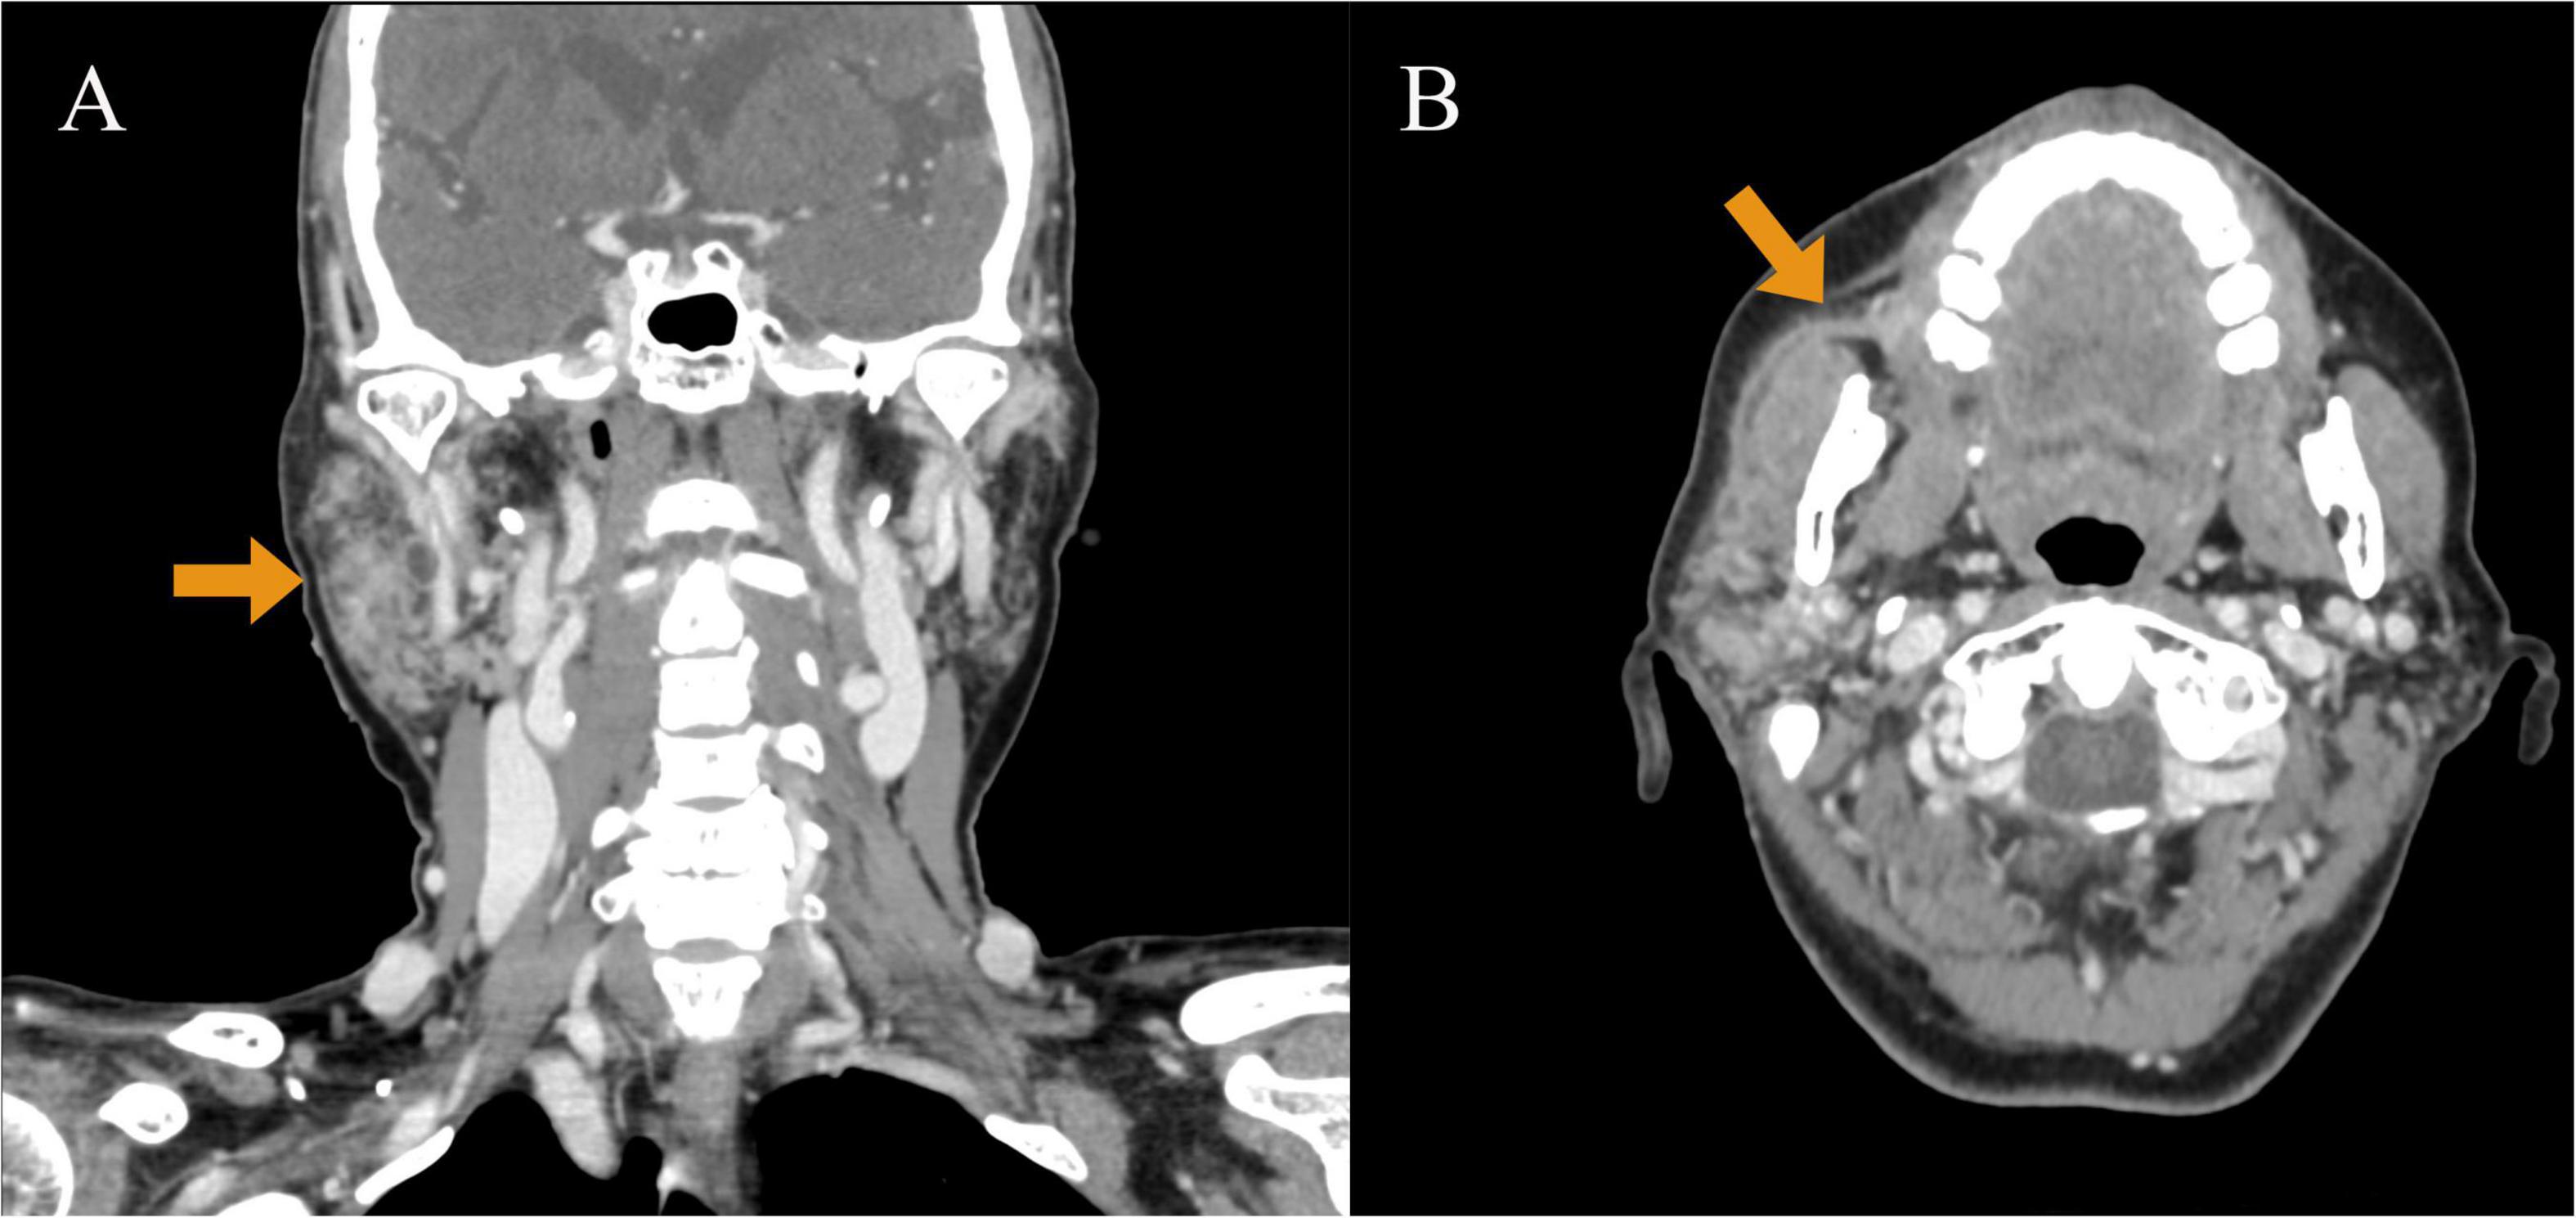

Background: Acute suppurative parotitis is common in primary Sjögren syndrome due to parotid gland dysfunction. Streptococcus gordonii is an aggressive pathogen but is rarely reported in acute suppurative parotitis. Case Summary: A 64-year-old woman with primary Sjögren syndrome, history of periodontitis, and recurrent parotid swelling developed acute suppurative parotitis from Streptococcus gordonii, quickly leading to sepsis. The pathogen was confirmed via pus and blood cultures, and effective antimicrobial treatment was initiated promptly, controlling the condition. Conclusion: This case highlights the rapid progression of Streptococcus gordonii-induced acute suppurative parotitis to sepsis, emphasizing the importance of primary Sjögren syndrome screening and managing periodontal infections in patients with recurrent parotid swelling.